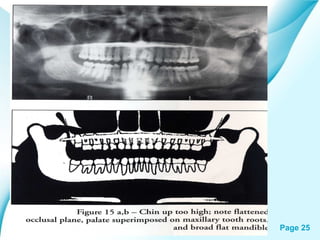

Positioning errors

( lips and tongue )

Powerpoint Templates

Page 30